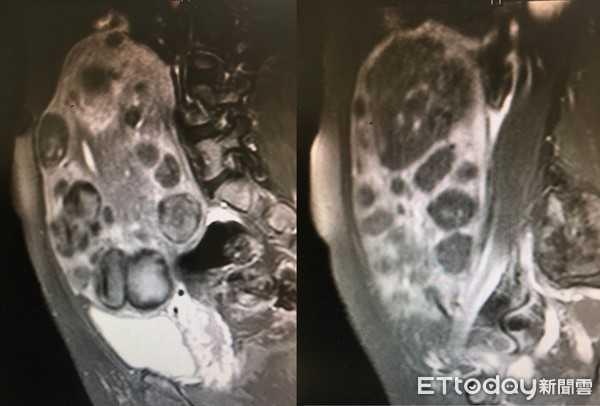

| Hình ảnh u xơ tử cung chụp qua MRI. Ảnh: Ettoday. |

Kết quả chụp MRI cho thấy trong lòng tử cung chứa khoảng 100 u xơ với nhiều kích thước khác nhau, u to nhất có đường kính 19 cm. Xét nghiệm máu cho thấy chỉ số hồng cầu của cô chỉ ở mức 7 gm/dl, một mức rất thấp thường chỉ gặp ở bệnh nhân thiếu máu.